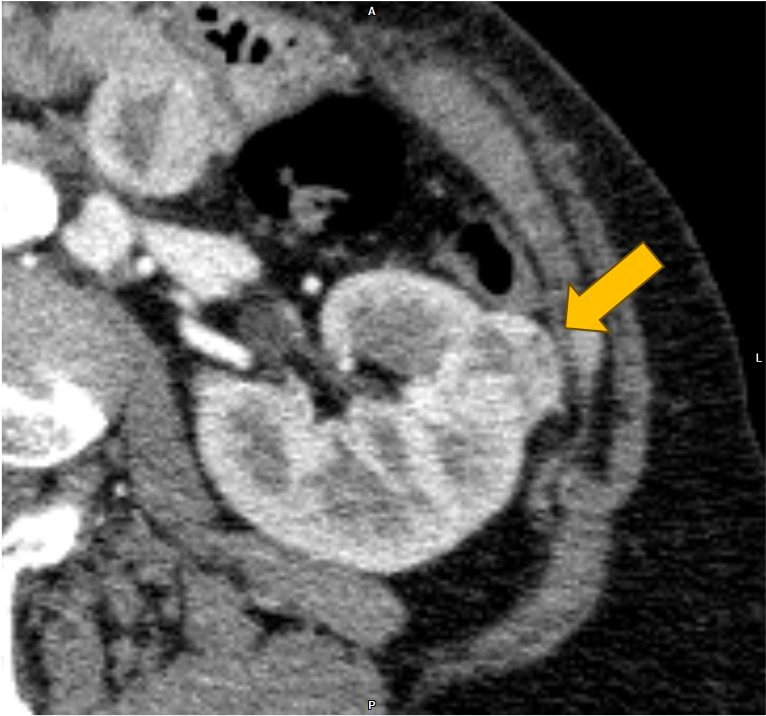

右腎癌(淡明細胞型腎細胞癌)術後の経過観察中に、左腎、膵尾部、胸骨の腫瘍が明らかとなり、胸骨病変の組織診断により右腎癌の転移の確定診断となった。本CTは化学療法中の治療効果判定目的に施行された腎ダイナミック造影CTである。

当該疾患の診断における造影CTの役割

右腎癌術後(淡明細胞型腎細胞癌)、左腎、膵体部、胸骨背側に腫瘤を認める。造影CTにおいての膵実質との増強効果の違いにより膵腫瘍を描出することができる。膵腫瘤はDynamic造影で早期濃染色、washoutパターンを呈しており、乏血性の造影パターンを呈す通常の膵癌との鑑別は容易である。